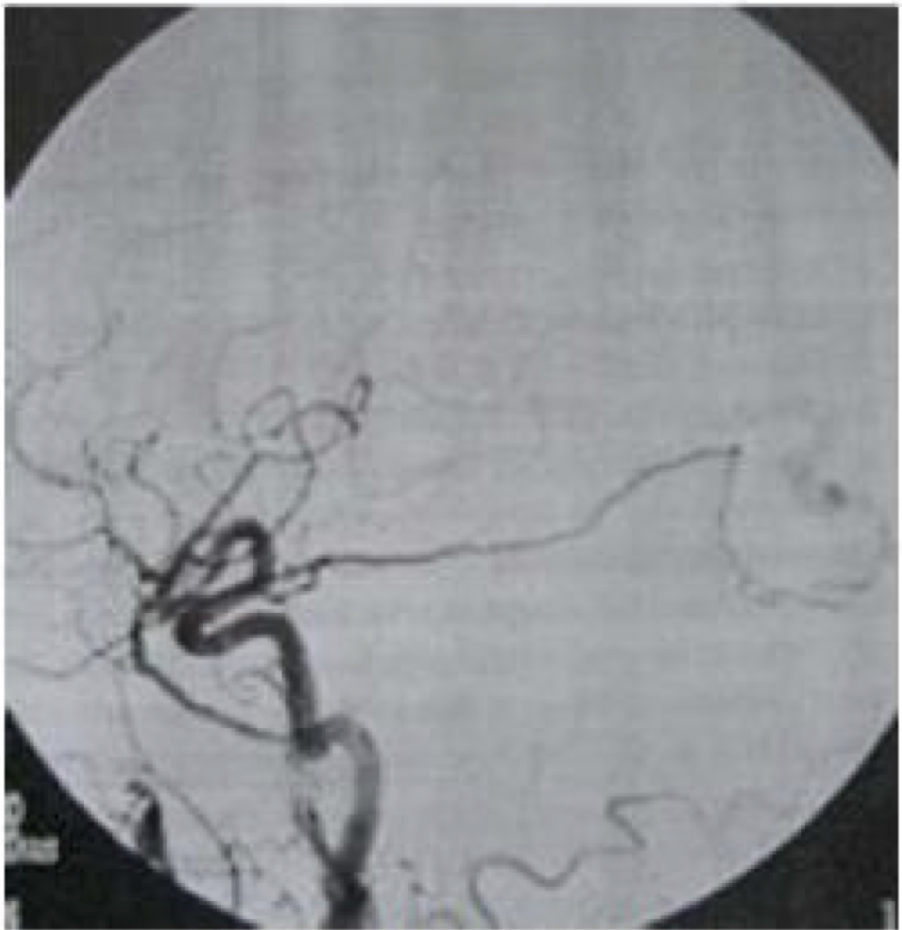

Gambar di bawah ini menunjukkan penyakit ?

A. AVM

B. Carotid Occlusion

C. Dural AVM

D. Meningioma

E. Moyamoya disease

D